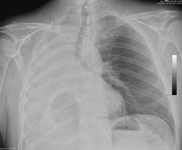

Рентгенография грудной клетки, показывающая окклюзию эндобронхиального стента правого главного бронха из-за слизи

Из коллекций Хосе Фернандо Сантакруза, дипломированного врача, члена Американской коллегии специалистов в области торакальной медицины, DAABIP, и Эрика Фолка, дипломированного врача, магистра наук; используется с разрешения